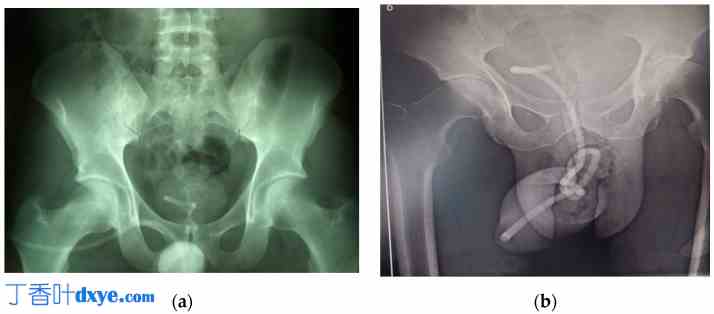

两例均在放射学检查中发现膀胱内有电缆,电缆有结和环(图 3)。病例 1 中的结直径约为 15 毫米,而病例 2 中的结直径约为 20 毫米。超声成像显示病例 1 中的膀胱内有一个结,但病例 2 中看不到。未进行 CT 扫描。

图 3。

3.jpg

KUB X 光显示膀胱内电缆的不透射线外观:(a)在病例 1 中,结位于膀胱颈的投影区域,(b)而在病例 2 中,结位于更靠尾部的位置。这是一张图。方案遵循另一种格式。